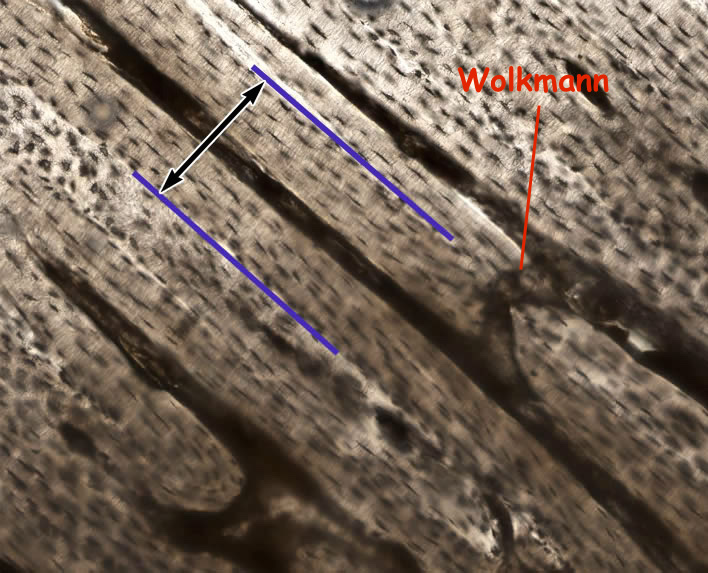

En fait ce sont des canaux qui relient deux canaux de Havers, ils sont donc perpendiculaires à ceux ci et à l'axe de la diaphyse.

Après tout dépendra de la coupe :

Si tu as une coupe transversale qui passe par un de ces canaux ça donnera ça (en 2)

Et si tu as un coupe longitudinale ça donnera ça (tu vois vraiment le lien entre 2 canaux de Havers)